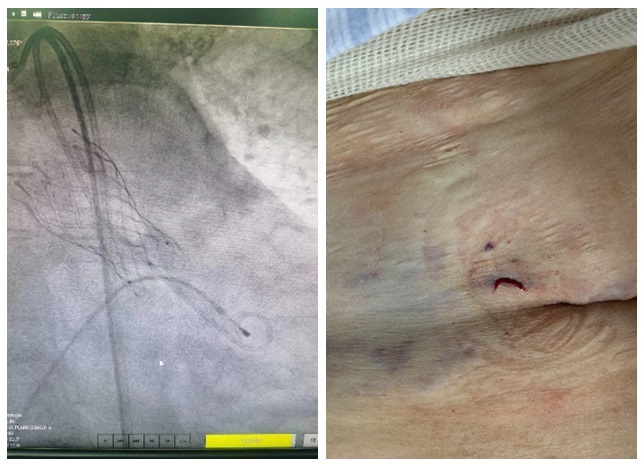

术前,心内科TAVR团队在反复论证手术的可行性后,向院委会及医务部提出了手术申请,并获得同意。在院领导的大力支持下,医务科组织了心内科、心胸外科、血管外科、麻醉科、影像科等多学科会诊,从诊疗方案到解剖结构、手术入路、手术风险、并发症的预防等各个方面进行了深入的分析和讨论。为确保手术安全,术前将每一个细节及可能发生的风险都做好了应急预案。术中,在广东省人民医院罗建方教授的指导下,经股动脉穿刺,心内科TAVR团队顺利通过介入导管将特制的人工瓣膜送到主动脉瓣的位置,来代替原来有病变的主动脉瓣工作。术前患者主动脉跨瓣压差高达60mmHg,术后立即降为0。经食道超声检查确认瓣膜扩张良好,无瓣周返流。患者术后很快恢复清醒,生命体征平稳,安返CCU。